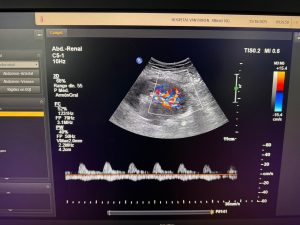

La Dra. Pilar Musalem, nefróloga coordinadora del programa de Trasplante Renal del Hospital Carlos Van Buren, explicó que “Los pacientes con enfermedad renal crónica tienen mayor riesgo de infarto agudo al miocardio, accidentes cerebrovasculares y mortalidad, además de poder progresar a una insuficiencia renal avanzada que requiera diálisis o trasplante. Detectarla a tiempo es clave para evitar estas complicaciones. Lo ideal es que quienes requieren diálisis puedan acceder a un trasplante, ya que esto mejora de manera significativa su calidad de vida y su sobrevida”